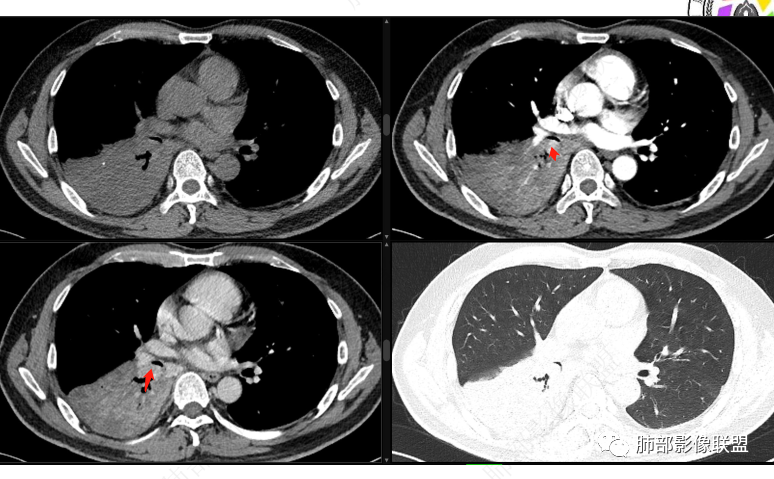

右肺下叶实变,周围磨玻璃,近端支气管扩张,管壁凹凸不平,远端阻塞,可见粘液栓,不均匀强化,有低密度无强化影,其内血管显示尚可,考虑粘液腺癌,鉴别淋巴瘤

右肺下叶大片实变,密度不均匀,可见支气管充气征及粘液区,右肺下叶支气管内结节影,下叶支气管阻塞,病灶前下可见磨玻璃影,右侧积液,考虑粘液腺癌,鉴别类癌?

中央型肿瘤pk周围型肿瘤  。壮年男性,热咳一周伴气喘,中性白细胞升高,临床是个感染过程。支持中央型病变的证据:1  肺门明显强化结节 2 横s征  3 支气管粘液栓  4 主支气管变窄,似见冰山征      支持周围型病变:1 按叶段塑形  2 血管造影征  3 病灶内弥漫高强化  4 周围伴磨玻璃灶,但境界不清继发感染?误吸?综合 中央型肿瘤可能大:类癌》鳞癌

右肺下叶支气管见结节灶继发右肺下叶膨胀不全,右肺中央局部炎性改变,下叶支气管结节动脉期明星强化,静脉期强化减低,首先考虑肺鳞癌,鉴别类癌、粘液表皮样癌。

首先血管未见明显侵犯、移位,提示病灶:炎性;肿瘤:外朝内——含粘液类腺癌(肺门淋巴结转移),腔内肿瘤(鳞癌、腺癌、类癌、小细胞、粘液表皮等)

从强化看:外周密度低,强化弱

就不太符合腔内肿瘤远端不张的表现,因为外围不张——强化明显

这一例反了

按这个特点周围要考虑肿瘤组织

腔内肿瘤,远端堵塞